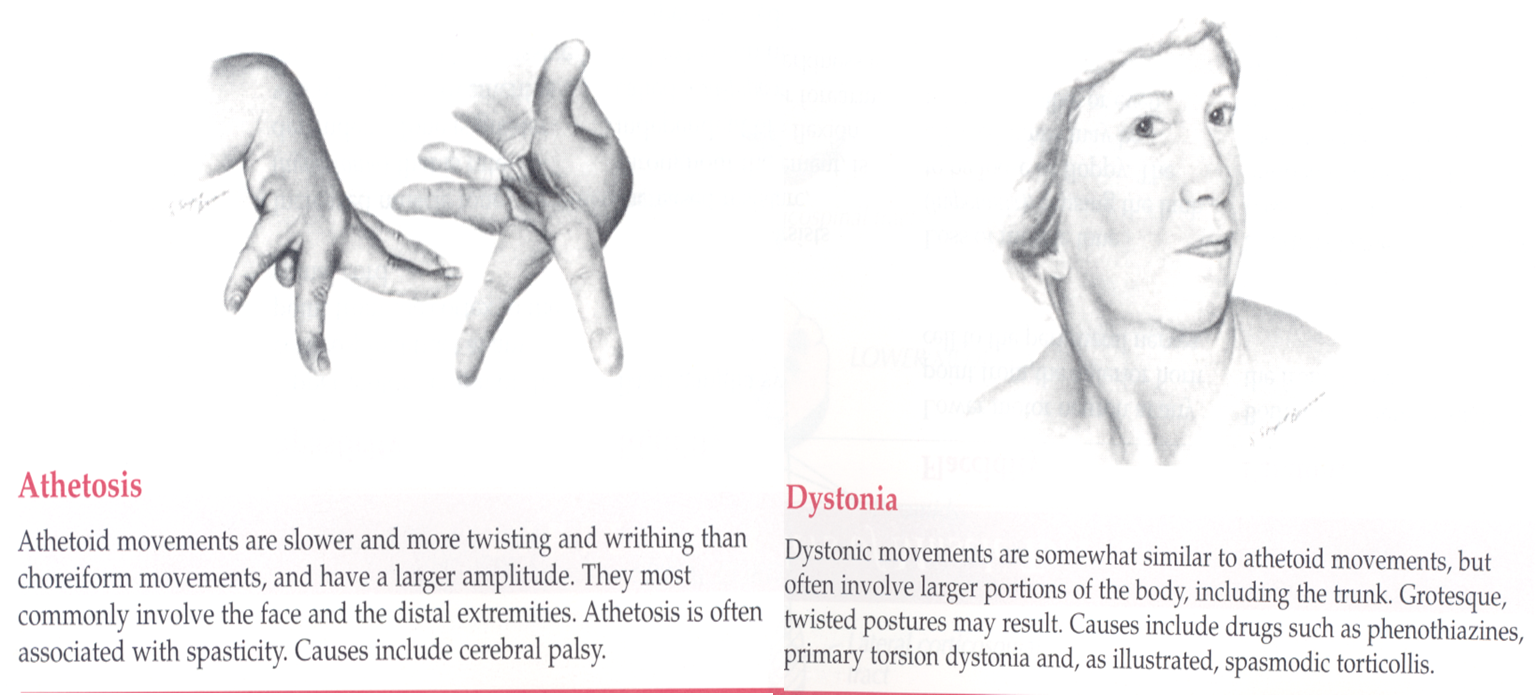

Involuntary movements

- location, quality, rate, rhythm, amplitude

Abnormal Movements

Cerebellar vs. Basal Ganglia lesions

| Basal Ganglia | - Involuntary movements |

| - Resting tremor | |

| - Chorea | |

| - Athetosis | |

| - Hemiballismus |